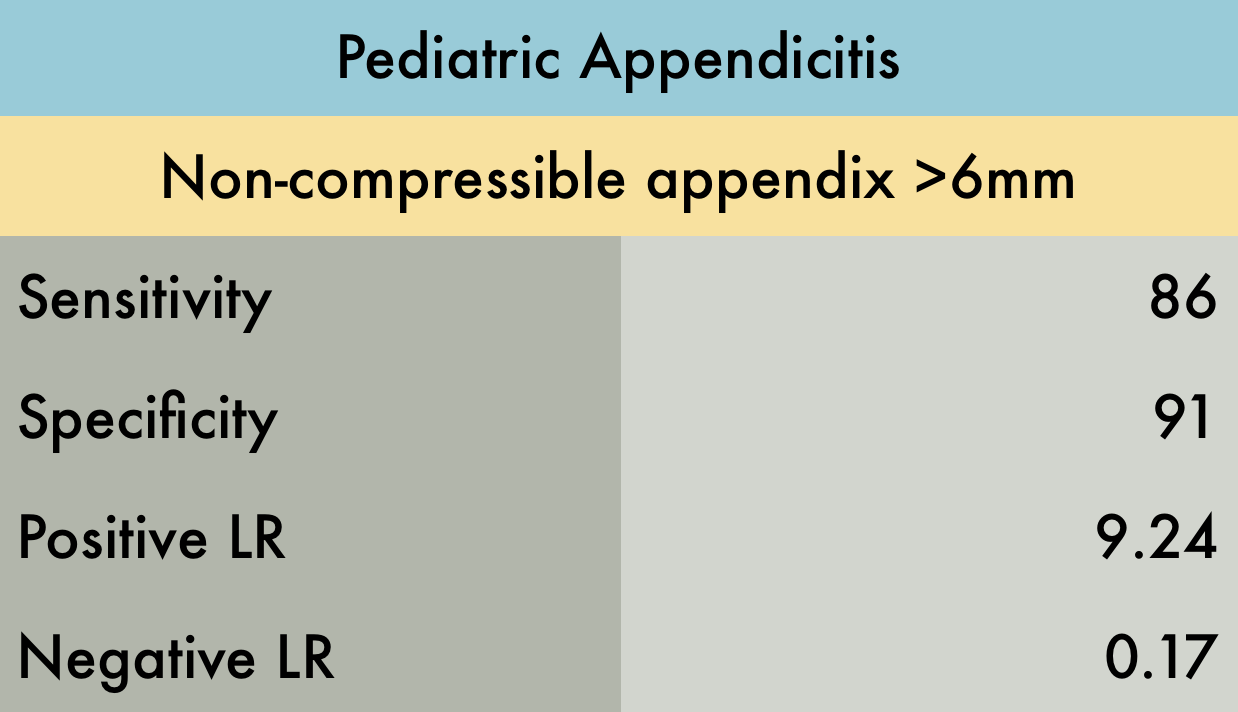

In a systematic review and meta-analysis of four studies including 461 pediatric patients, POCUS by emergency physicians had 86% sensitivity and 91% specificity. The positive and negative Likelihood Ratios (LR) were 9.24 and 0.17, respectively. All included studies were prospective and were moderate to high quality (1).

Using this data, POCUS can diagnose acute appendicitis, without the need for radiologist-performed ultrasound, CT, or MRI. However, if POCUS is equivocal or negative, appendicitis cannot be ruled out without further studies. (1)